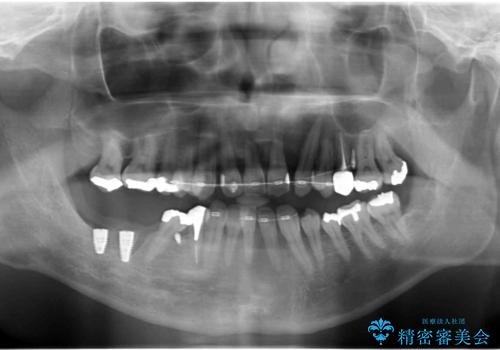

前歯の部分矯正を行い受け口を改善しました。

奥歯まで動かそうとすると顎の手術の適応になってしまうため、奥歯はそのままにして前歯のかみ合わせを改善しました。

また、奥歯はインプラント治療を行い、矯正で下の前歯を後ろに下げるのに使用しています。

右下のインプラント治療は横浜桜木町歯科院長大元先生にお願いしています。

通常骨格的な受け口を部分矯正でというのは不可能なことが多いのですが、今回はいろいろな条件が重ねなりお引き受け可能でした。通常は難しいです。